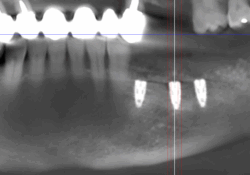

Lorsque l’os de la mâchoire est insuffisant pour soutenir un implant dentaire, des techniques de reconstruction osseuse peuvent être nécessaires. Ces procédures permettent d’augmenter le volume osseux pour garantir la stabilité de l’implant.

- Greffe osseuse : Ajout d’os ou de matériaux pour augmenter le volume osseux.

- Régénération Osseuse Guidée : Stimule la repousse osseuse grâce à des biomatériaux.

- Sinus Lift : Augmentation de l’os dans la région des molaires supérieures par élévation des sinus.